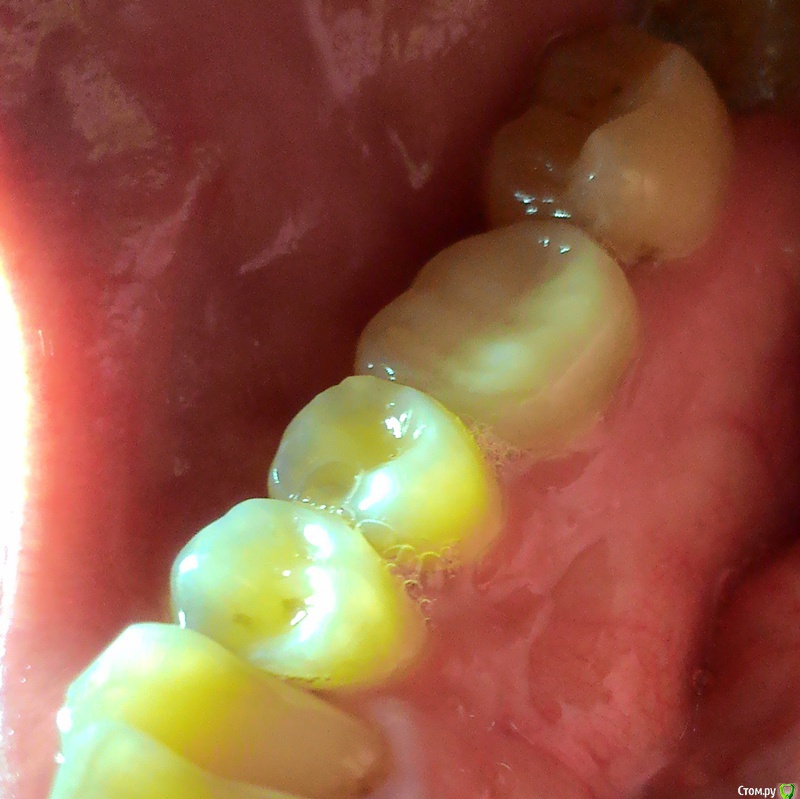

Snomov Опубликовано 28 июля, 2015 Поделиться Опубликовано 28 июля, 2015 (изменено) Здравствуйте! Вылечили мне на днях зуб, шестерку справа внизу, зуб теперь мертвый, пломбировали каналы. Сама пломба довольно крупная, насколько я понял, изнутри (со стороны языка) этот зуб довольно сильно обточили и соприкасание с зубом антагонистом изнутри нет. Снаружи (со стороны щеки) соприкасание хорошее, в общем ничего не мешает.Есть сомнения, насколько это нормальная ситуация, и есть ли смысл повторно обращаться к врачу?Дело еще и в том что этот зуб начали лечить после скола как раз на наружной стороне, как сказали был кариес и еще из-за чрезмерных нагрузок на него, так как слева внизу пятерка и шестерка удалены и ожидается имплантация.Подскажите что делать, и если нужно исправлять, то насколько срочно, так как сейчас я в командировке и к делавшему пломбу врачу нужно специально ехать. Изменено 28 июля, 2015 пользователем Snomov Ссылка на комментарий

Snomov Опубликовано 28 июля, 2015 Автор Поделиться Опубликовано 28 июля, 2015 http://forum.stom.ru/topic/20613-sovety-patcientam-obiazatelno-k-prochteniiu/Сделал и добавил фото, ничего более наглядного предоставить не смогу. Ссылка на комментарий

red_butler Опубликовано 28 июля, 2015 Поделиться Опубликовано 28 июля, 2015 зуб требует протезирования, следующего скола он не переживет 1 Ссылка на комментарий

DmitrySH Опубликовано 28 июля, 2015 Поделиться Опубликовано 28 июля, 2015 Зубы с большой потерей твердых тканей - нуждаются в ортопедическом восстановлении. Рассматривайте эту конструкцию, как временную. После имплантации - комплексное ортопедическое лечение.Да, от 8-ки избавляйтесь скорее. Иначе 7 зуб сильно пострадает, если еще не начал. 1 Ссылка на комментарий